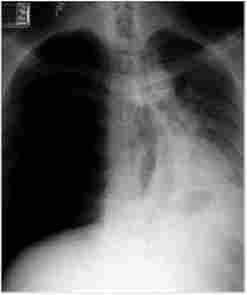

Мал. 253. Рентгенівське зображення правостороннього напруженого пневмотораксу

Остаточне підтвердження діагнозу відбувається після проведення рентгенівського дослідження грудної клітки (рис. 25.3).

При рентгенографії легень на боці пневмотораксу визначається зона просвітлення, позбавлена легеневого малюнка на периферії і відокремлена чіткою межею від спавшегося легкого; зміщення органів середостіння в здорову сторону, а купола діафрагми - донизу; розширення геміторакса, девіація трахеї в бік здорової легені. Якщо при проведенні діагностичної плевральної пункції отримують повітря, то відповідно до цієї ознаки і виявленими при фізикальному обстеженні симптомами діагноз пневмотораксу стає переконливим.